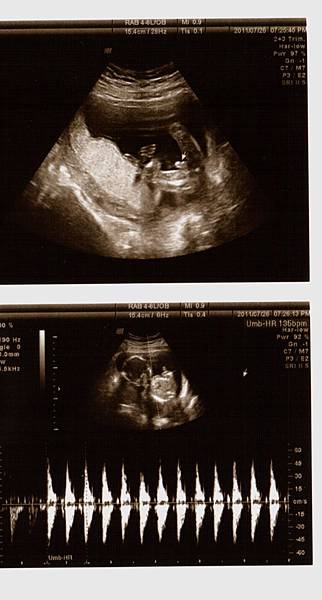

接著,重頭戲來囉,黃醫師幫我照了超音波,躺在床上的我和站在一旁的老公顯得緊張,當我還在思考等一下醫生會告訴我寶寶究竟是男是女之際,思路還來不及轉彎之時,黃醫師就已迅雷不及掩耳的速度告訴我:『這是男寶寶喔!』我驚訝的不得了!還說『怎麼看啊?在哪在哪?』醫生不急不徐地說:『這是寶寶的弟弟,有看到凸出來的,那就是弟弟喔!』天啊,是弟弟啊(說實在,我真想看看老公當時的表情><)接著,醫師告訴我寶寶的頭偏大,看來是個大頭弟,大腿骨普通長(媽媽我還以為他是個長腿男勒!),然後醫師拿著探頭四處看,告訴我寶寶的一切都正常,讓媽咪我放心了許多!

一連串拿了七張超音波照片,還看了4D的超音波,真是超棒的唷!!!